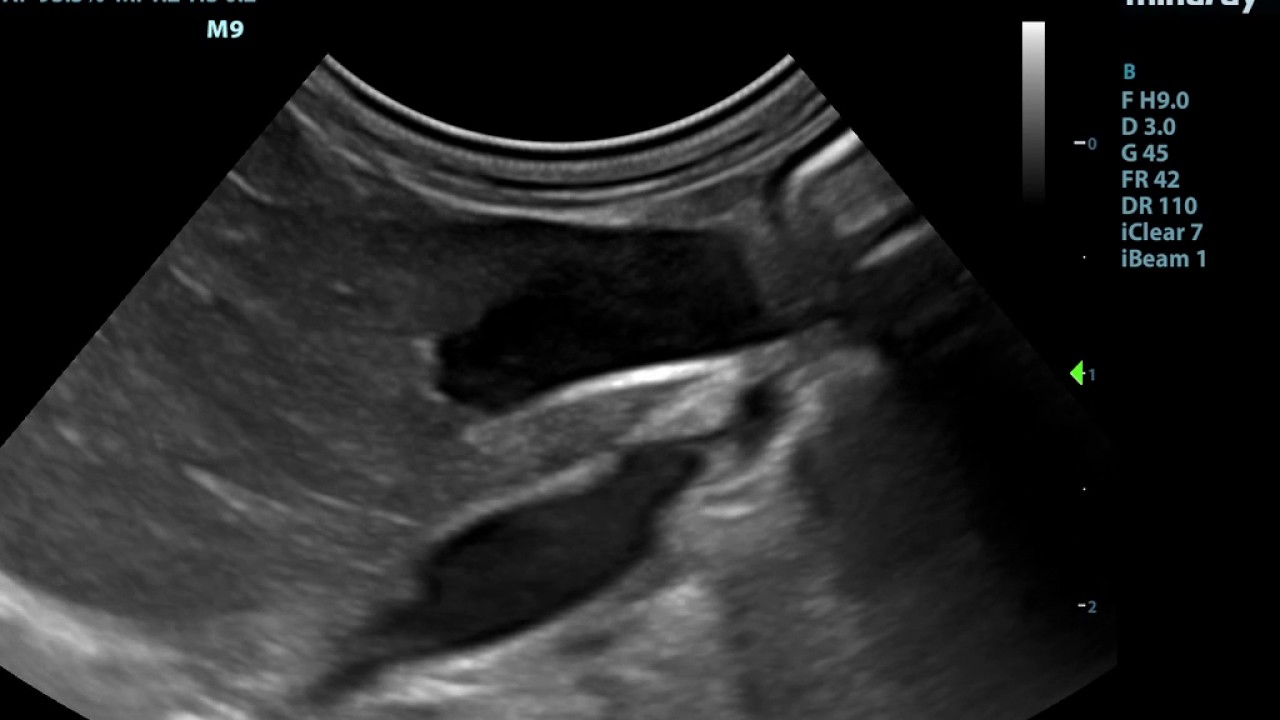

Clarius Vet Small Animal Ultrasound Liver Scan YouTube Small Animal Ultrasound.com Atlas of small animal ultrasonography, second edition is a comprehensive reference for ultrasound techniques and interpretation of disorders in. The references are open access and no log in or registration is required. Learn, exchange and collaborate on small animal ultrasonography with this website and its companion book. Welcome to the companion website for. 1m+ visitors in the past month To. Small Animal Ultrasound.com.